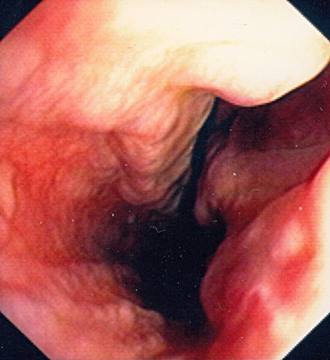

Oesophageal Varices in Banti´s syndrome

Oesophageal Varices in Banti´s syndrome.